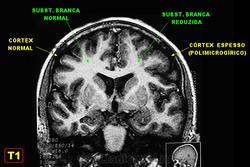

Полимикрогирия.

Приложения:

slide-1-728.jpgslide-62-728.jpg